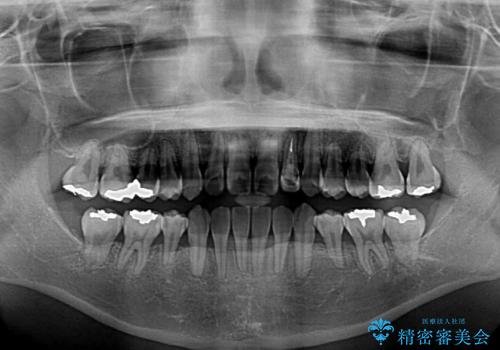

- 下顎の歯が舌側に倒れていることと、前歯の咬み合わせの不具合を気にして来院された患者様です。

受け口傾向の口元であるため、下顎左右小臼歯各1歯を抜歯して歯列を整えることとしました。

前歯には治療中の仮歯が装着されていたため、矯正治療後にオールセラミッククラウンにて補綴治療を行うこととしました。